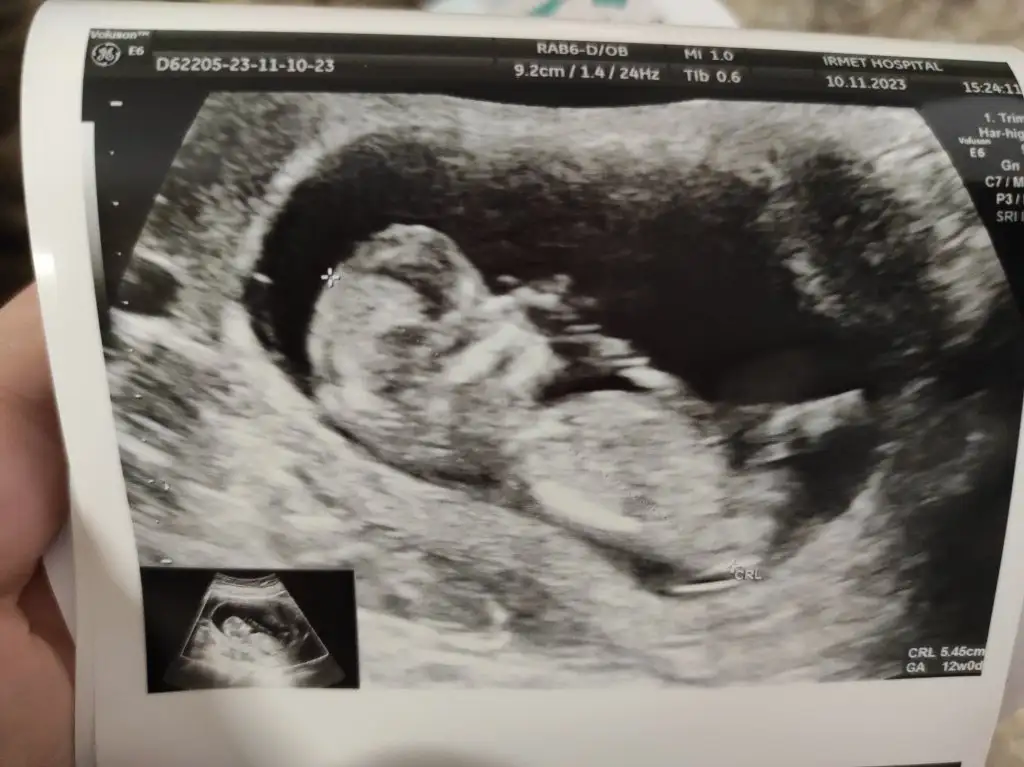

Cinsiyet tahmini olan var mı 12. Hafta🥰

Eklentiler

• IMG_20231110_155302_1.webp

IMG_20231110_155302_1.webp

32,8 KB · Görüntüleme: 128